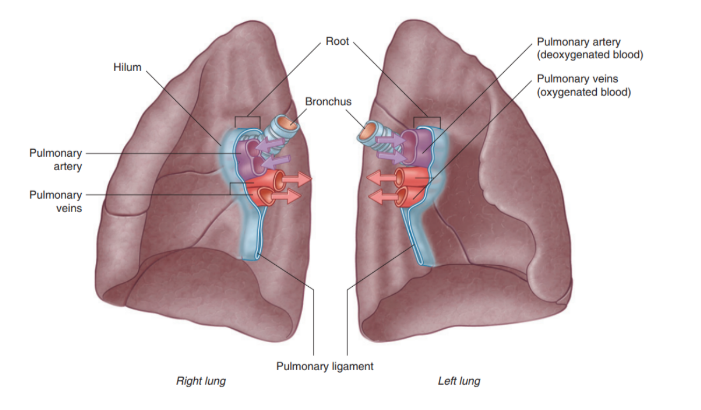

Root + hilum

The root —

A short tubular collection of structures attaching each lung to structures in the mediastinum

Covered in a sleeve of mediastinal pleura reflecting onto the lung surface as visceral pleura

Originates the pulmonary ligament — thin blade-like pleural fold projecting from the root towards the mediastinum, functioning to stabilize the position of the inferior lobe

The hilum —

The region outlined by this pleural reflection on the medial lung surface — where structures enter & leave

Structures we can find in each root & hilum —

Pulmonary artery

2 Pulmonary veins

Main bronchus

Bronchial vessels

Nerves

Lymphatics

The pulmonary artery is in most cases found at most superior portion of the hilum, while the pulmonary veins are inferior & the bronchi are posterior

On the side side however, the lobar bronchus to the superior lobe branches from the main bronchus in the root, unlike on the left where it branches in the lung itself superiorly to the pulmonary artery

Overall vasculature of the lungs image

Pulmonary arteries (overall)

1 right, 1 left, originate from the pulmonary trunk & carry deoxygenated blood to the lungs from the right ventricle of the heart

Bifurcation of pulmonary trunk occurs to left of midline just inferior to vertebral level TIV/V, and anteroinferiorly to the left of the bifurcation of the trachea

Right vs left pulmonary arteries

Right pulmonary artery —

Slightly longer than left

Crosses horizontally at the mediastinum passes anteriorly & inferiorly to the bifurcation of the trachea, & anteriorly to the right main bronchus — also posteriorly to the ascending aorta, superior vena cava, and upper right pulmonary vein

Enters into root of lung giving off a large branch to the superior lobe of the lung

Main branch continues through hilum to give off a second recurrent branch to superior lobe before dividing to supply both the midline & inferior lobes

Left pulmonary artery —

Shorter than the right, anterior to the descending aorta & posterior to the superior pulmonary vein

Pulmonary veins —

On both sides — superior & inferior pulmonary vein

Carry oxygenated blood from lungs back to heart

Begin at hilum, pass through root of lung, & immediately drain into left atrium